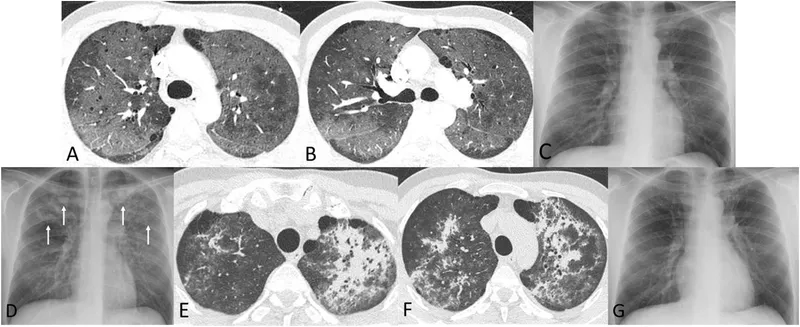

| Diagnosis | CXR: bilateral, diffuse interstitial infiltrates ("bat-wing"). ↑ LDH (>200 U/L). Definitive: BAL with silver stain. |